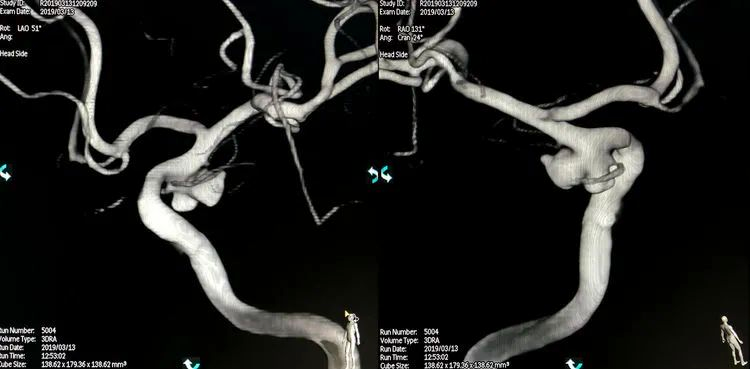

2019年3月13日行DSA+介入治疗。术前左颈内动脉造影三维重建显示左侧后交通动脉瘤,呈牛角形分叶;后交通动脉由瘤颈近心端发出,非胚胎性: